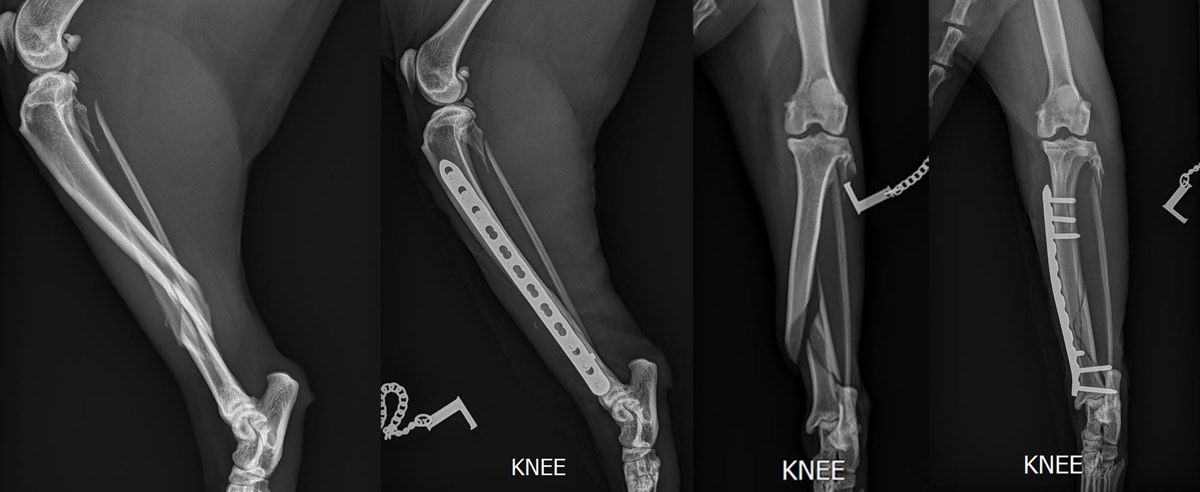

- Bildgebende Verfahren

• Röntgenaufnahmen

- Leeraufnahmen

- Stressaufnahmen